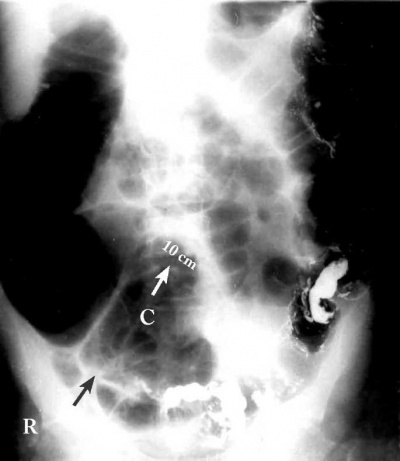

צילום בטן סקירה - מראה התרחבות של הכרכשת עד לגובה החסימה. אם המסתם האילאוצקלי אינו פועל, ניתן לראות תמונה המתאימה גם לחסימה מעורבת של המעי הדק והכרכשת או תמונה המתאימה לחסימה מדומה (תצלום 6.6).